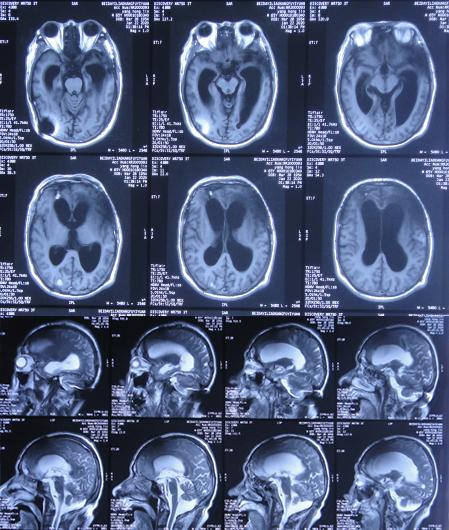

在第3家医院康复治疗近1个月时间内,曾4次查头颅影像(2020年1月22日( 图-24 )、2020年1月29日( 图-25 )、2020年2月10日( 图-26 )、2020年2月19日( 图-27 ))均示脑室仍有扩张,但未给予特殊处理。

图-24: 2020年1月22日头颅核磁

图-25: 2020年1月29日头颅CT

图-26: 2020年2月10日头颅CT

图-27: 2020年2月19日头颅CT

但住院期间间断性发热仅给予药物后仍反复,且大小便时有*禁失**,因此于第3家医院治疗28天后即2020年2月19日,转回当地的第4家河北省邯郸市某三甲医院治疗。

在第4家医院治疗26天,仍间断性发热、大小便*禁失**加重,住院期间曾2次查头颅CT(2020年2月27日( 图-28 )、2020年3月12日( 图-29 ))示脑室仍扩张。

图-28: 2020年2月27日头颅CT

图-29: 2020年3月12日头颅CT

治疗期间给予抗生素,并多次腰椎穿刺,脑脊液培养示无菌,发热虽有好转但大小便*禁失**无改善,且意识变模糊。经当地医生介绍转住入北京北亚骨科医院的李小勇脑脊液科。